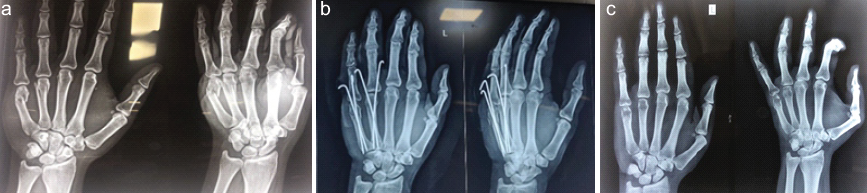

Post-operative immobilization was done with a volar splint for 4 weeks by protocol in fear of loss of fracture reduction. Out of 20 cases, three cases needed percutaneous reduction of fracture. Initially, for the first six cases, we used only single K-wires, and after we started using multiple K-wires (Fig. 2a, b, c).

Figure 2: (a) # of 4th, 5th metacarpal shaft, (b) fixed with multiple K-wires, and (c) after wire removal at 10th week.